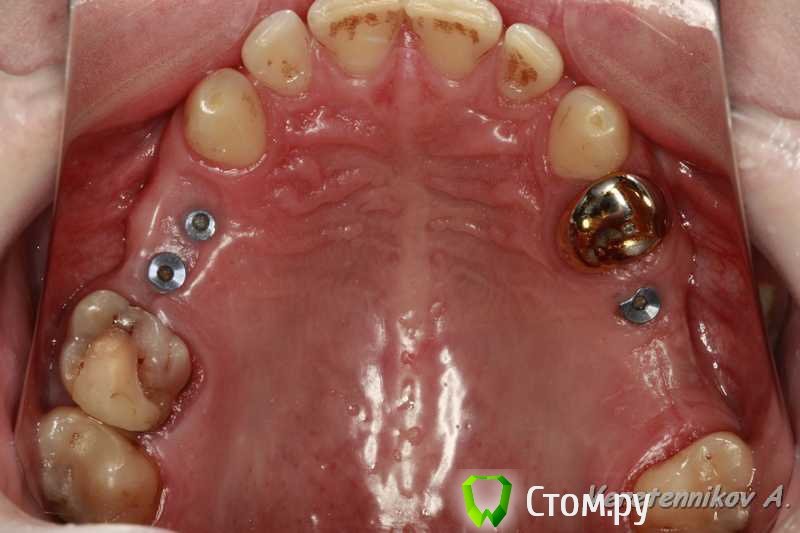

an_ver Опубликовано 15 сентября, 2014 Автор Поделиться Опубликовано 15 сентября, 2014 Вот такая картина на сегодня Ссылка на комментарий

Чертков Александр Опубликовано 15 сентября, 2014 Поделиться Опубликовано 15 сентября, 2014 Вот такая картина на сегодня Андрей, ИМХО, сст не "вывезет".... Ссылка на комментарий

Тимур86 Опубликовано 15 сентября, 2014 Поделиться Опубликовано 15 сентября, 2014 а мне кажется прокатить может... Ссылка на комментарий

TIGER Опубликовано 15 сентября, 2014 Поделиться Опубликовано 15 сентября, 2014 Заживало видимо вторичным натяжением? Ссылка на комментарий

Дмитрий Никитюк Опубликовано 15 сентября, 2014 Поделиться Опубликовано 15 сентября, 2014 Не смертельно. Тут даже после установки фдм ситуация улучшится. Резорбция не страшна, пока поверхность имплантата не инфицирована. Считайте, что у Вас уже произошло ремоделирование. Подсадка ССТ спасёт ситуацию. 4 Ссылка на комментарий

Aquarius Опубликовано 15 сентября, 2014 Поделиться Опубликовано 15 сентября, 2014 Полностью согласен, ставьте ФДМы и все. Если заморочиться, то можно и ССТ . А так Дмитрий прав, все самое страшное ( ремоделировка))) по сути уже позади Ссылка на комментарий